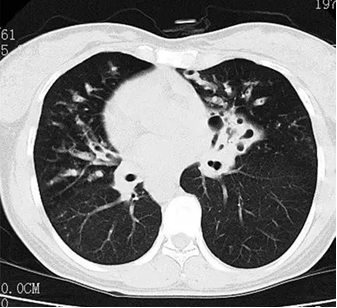

按下自己激动而复杂的心情,我还是给患者开了血常规、血气分析、肺功能检查、胸部 CT 和痰培养。很快,血常规结果显示白细胞数量、中性粒细胞比例、CRP 升高,考虑细菌性感染。血氧饱和度 95%,肺功能检查显示轻度限制性通气功能障碍及弥散功能障碍。胸部 CT 结果报告显示「双肺纹理增多紊乱,双下叶支气管扩张,并树芽状结节」,同时进一步证实右位心,很明显看到心脏偏向右侧。心脏没有问题,心音和瓣膜音也很正常。

胸部 CT 平扫示:双下叶支气管扩张伴感染,右位心。(注:胸部 CT 横断面的图相当于是从脚看向头部,因此图上的左右是相反的;图源:参考资料 2,非本病例)